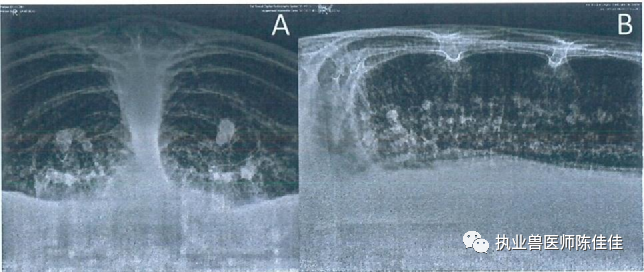

海龟医疗怎么样海龟经壳肠穿刺抽气治疗浮水_https://www.jmylbn.com_新闻资讯_第1张获得背腹,前后,侧和颅骨X放射图。X光片显示整个胃肠道矿物质混浊增加的部分,并有远端结肠嵌塞的证据。还存在明显气体膨胀的节段,导致左肺野背侧移位和压缩。右肺表现出肺部疾病的影像学征象,表现为与肺炎一致的弥漫性间质模式(图1)。

图1显示胃肠道气体膨胀的初始前后位X线片(A);注意左肺的背侧移位和压迫。整个右肺野以及压缩的左肺背野均存在非结构化的间质性肺模式和软组织混浊增加。(B) 初始侧视图。(C) 最初的背腹视图显示远端结肠有嵌塞。(D) 最初的背腹视图显示整个肠道中混合的矿物质和气体不透明物质以及肠道中的气体膨胀。(E) 最初的背腹视图显示整个左右肺野的非结构化间质肺模式。还可以看到气体膨胀的肠压迫左肺。